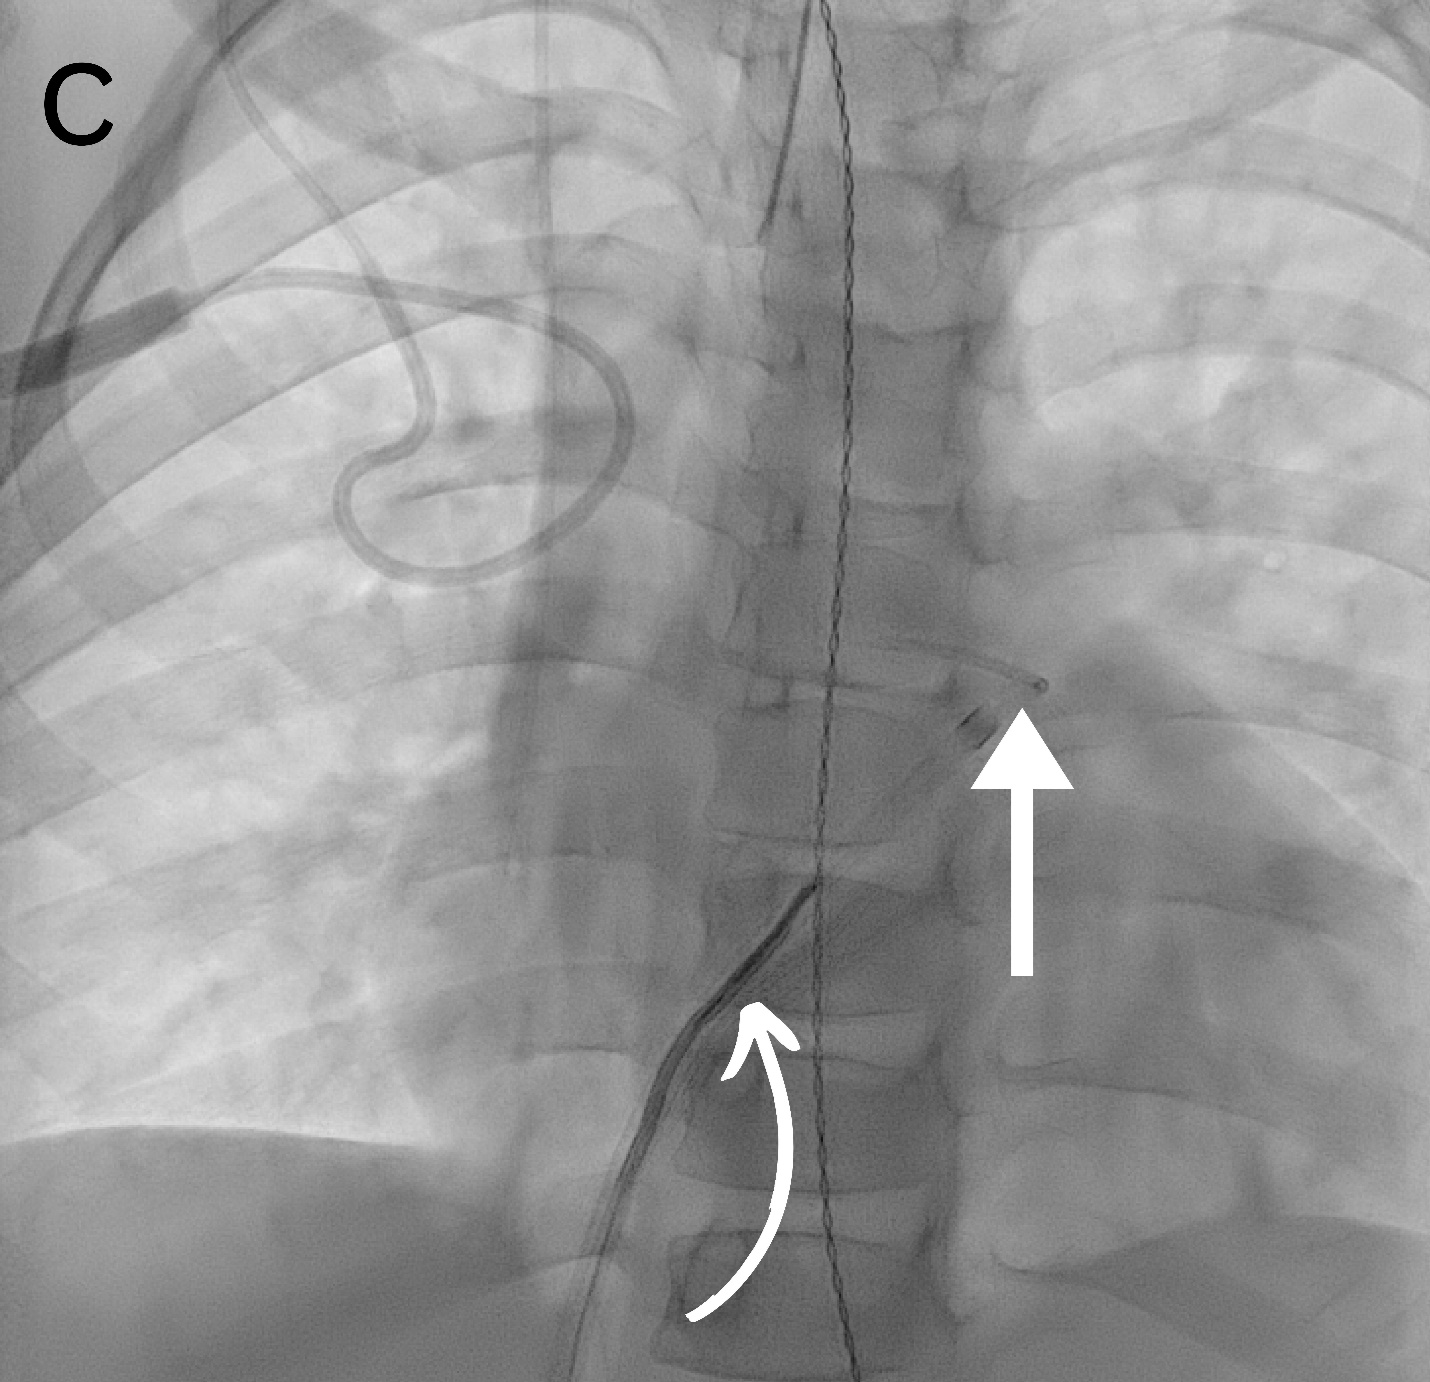

All the procedures were performed under general anesthesia. No prophylactic antibiotics were used for any procedures. Vascular access was obtained through the femoral veins. Ultrasound and fluoroscopy were the guidance modalities used in all (Figure). The retrieval sheath size ranged from 4 to 14 French (Fr). Various angled and reverse-angled catheters were used to reach the embolization site, with sizes ranging from 4 to 6 Fr. A snare was used to retrieve the foreign body in 8 cases, while a combination of snare, aspiration catheter, and suction device was used in 1 case. A single-loop snare device was used in all patients but one, in which a combination of single and tri-loop snare devices was used. The loop sizes of snare devices ranged from 6 to 25 mm. Hemostasis was achieved by compression in all cases. Heparin was not used for any of the cases.

Nine patients with a mean age of 8.56 years (SD = ± 4.25 years; range, 4-17 years) were included (Table). There were 5 male and 4 female patients. We observed an equal number of cases with embolized foreign bodies in the main, left, and right pulmonary arteries (3 cases each). Foreign bodies were present for 1 day from the day of identification in 6 patients, while 3 patients had foreign bodies in place for 2, 14, and 27 days, respectively. The most common type of foreign body was a port catheter (55.6%, n = 5), followed by a central line, a peripherally inserted central catheter (PICC), coils, and N-butyl cyanoacrylate (n-BCA) glue with Lipiodol (1 case each). All (n = 5) port catheters were initially placed in the subclavian vein. Of these 5 port catheters, 4 dysfunctioned after an average of 3.2 years (SD = 1.3; range, 1.2-4.2), while 1 dysfunctioned 15 days after placement. Catheter fracture was the most common (77.8%, n=7) cause of foreign body. Most (n = 5) catheters fractured spontaneously, while 2 fractured during attempted removal. The foreign body was identified using a plain radiograph in most cases (66.7%, n = 6), followed by fluoroscopy and angiography during the procedure (11.1%, n = 1 each). The foreign bodies were successfully retrieved in all cases. In the case of the embolized coils, a femoral cutdown was also required to remove the coil mass safely.

In one of our cases, n-BCA glue mixed with Lipiodol embolized from the iliac veins to the pulmonary arteries. Stable access was established via 10- and 12-Fr Check-Flo sheaths (Cook Medical) inserted through the popliteal and femoral veins to prevent further migration. Negative pressure aspiration was initially employed to remove the glue from the femoral and iliac veins. For fragments that had traveled to the pulmonary arteries, gooseneck snares were utilized to carefully retrieve the embolized material. An aspiration catheter (Penumbra, Inc.) was employed for more resistant fragments, enabling precise and focused suction directly within the pulmonary arteries. This combination of techniques ensured the effective and safe removal of the foreign body. The estimated blood loss was 300 mL. There were no immediate complications except transient arrhythmias during 1 procedure while maneuvering the catheter across the right atrium, which resolved independently.